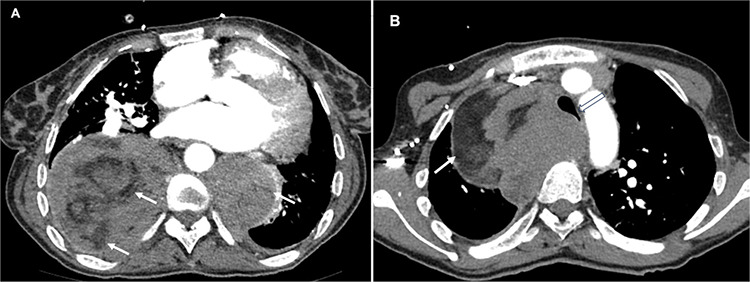

A Rare Cause of Giant Intrathoracic Mass in a Woman with Sickle Cell Disease: Extramedullary Hematopoiesis